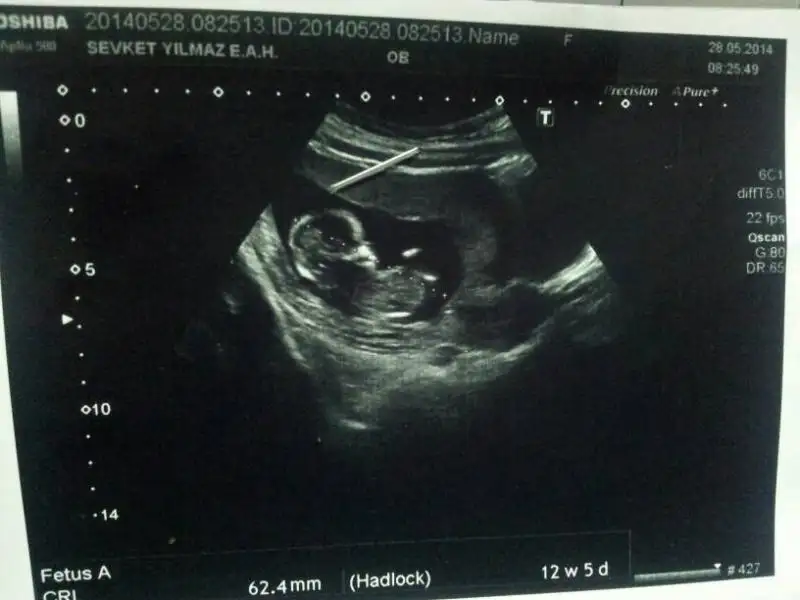

yani ikili testte yüzde seksen erkek dedi ama çok hareketliydi yerinde durmuyodu. 14 gün sonra dayanamadım bi daha gittim kıza benziyo ama bi ondan bi ondan tahmin yapmıcam en iyisi 16. haftayı bekleyelim dedi erkek olmasını çoooook istiyorum ALLAH kalbimi biliyo , elbette öncelikle sağlıklı ve sıhhatli olsun rabbim kucağımıza kavuştursun inşaallah tüm anneleri mutlu etsin Rabbim. İçimden hep oğlum demek geliyo ama bilemiyorum sizlerin yorumu iyi geldi bana teşekkür ederim

Anladım; yüklediğin resimde pipisi var gibi yani :) bana da ikili testte erkek dedi doktorum, çıkıntı çok belirgindi zaten.. İnşallah sonra kıza benziyo demez biz isim bile bulduk çünkü ;) İnşallah Allah her annenin gönlüne göre versin, senin de gönlündekini versin önce sağlıklı ve hayırlı olsun bebişlerimiz tabi ki :)

Evet canım doğru yeri kare içine almışsın ve bana da paralel gibi geldi büyük ihtimal kız bence de ama tabi burda çok küçük heralde doktorlar 13. Haftadan önce kolay kolay tahminde bulunmuyorlar, bi dahaki kontrolünde belirginleşir o zaman öğrenirsin :) Allah gönlüne göre versin sen de kız istiyosun galiba ama hislerin de çok önemli baştan kız hissettiysen kız olma ihtimali yüksek ben en baştan erkek hissettim bebeğimi doktor söyleyince şaşırmadım bile ama tabi herşeyin hayırlısı önemli olan sağlıklı olması, Rabbim hepimize sağlıklı bebekler nasip etsin

Kizlarinki paralel oluyo cnm erkeklerinki dik yuzde otuz dereceyle yani

Kızlar benim bebeğimin de cinsiyetini tahmin eder misiniz ? İkili test sırasında Oğlan'a benzettim ama bana güvenme dedi ultrasonu çeken doktor. Kendi doktorum değildi. Devlette yaptırmıştım ikili testi. Çok merak ediyorum.

İlk resimde 10+2 ydik.

ikinci resimde sat 13+2 ultrason 12+5 ti. Gerçi hep sat ile ultrason uyumlu gittim. Devletteki ultrason bozdu olayı :) $IMG.webp $1401271843618.webp